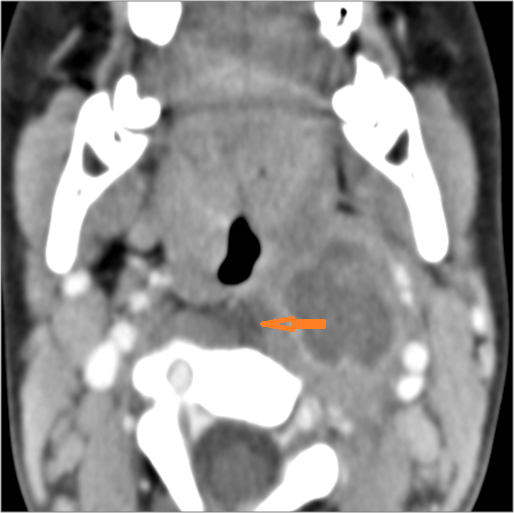

Vascular Findings

There is evidence of thrombus, thrombophlebitis or other occlusive or inflammatory process of the jugular vein. [Yes/No]

There is evidence of thrombus, thrombophlebitis or other occlusive or inflammatory process of smaller jugular venous tributaries. [Yes/No]